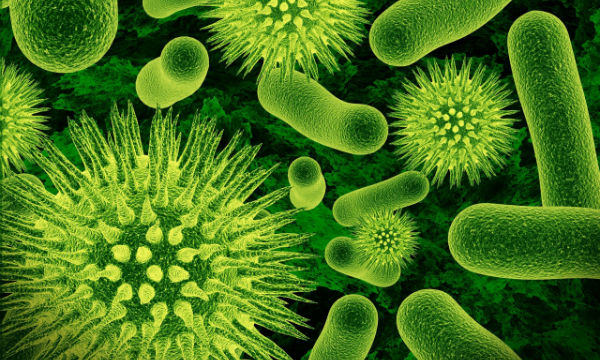

![]()

مرض